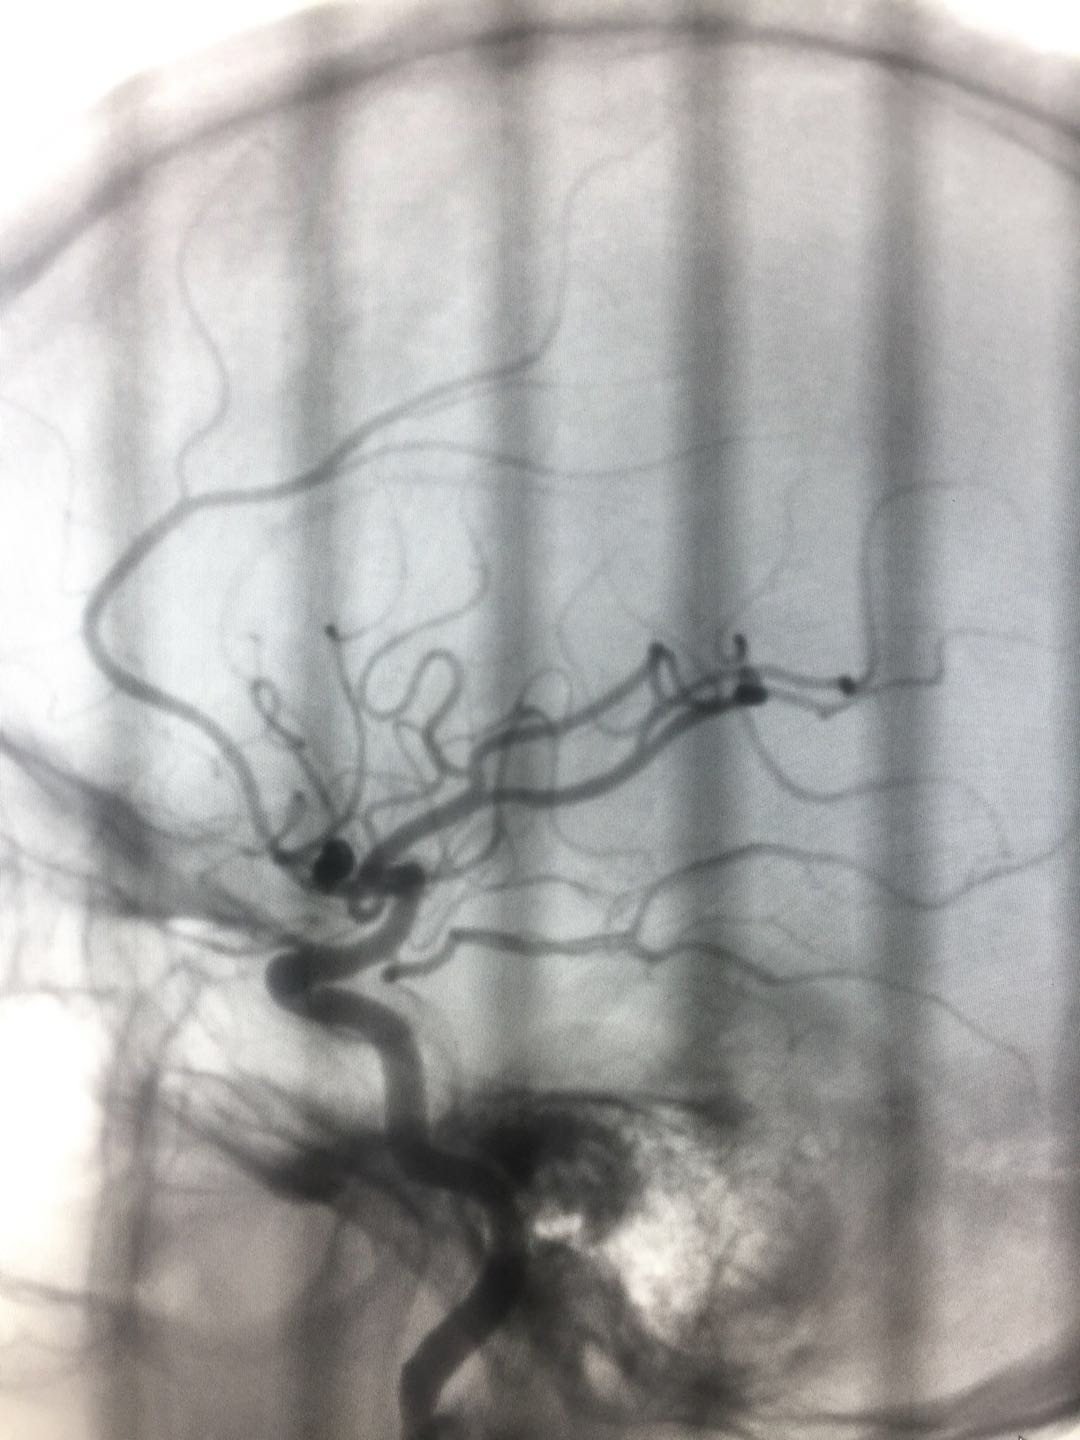

(术后)